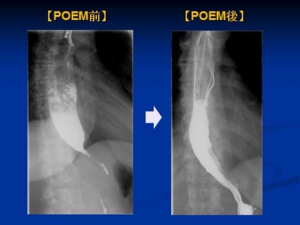

食道アカラシアとは下部食道括約筋の異常により、下部食道狭窄、下部食道弛緩不全が起こり、食事が食道から胃へスムーズに流れない病態です。薬物療法や、内視鏡的バルーン拡張術では治療効果が乏しいことが多く、一般的には根治術として外科手術(Heller-Dor法)が行われています。外科手術にて行ってきた筋層切開術を、内視鏡的に行ったものがPOEMであり、その有用性より外科手術に替わる標準術式になりつつあります。POEMは2008年に井上晴洋先生により初めて報告された処置であり、当科では2010年11月に導入し、計11例の症例に対して施行し、良好な治療成績を得ております。

《POEM前後の比較》